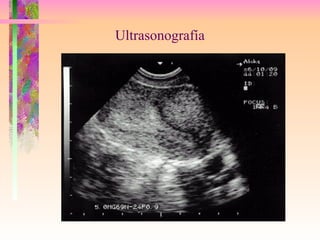

Ultrasonografía